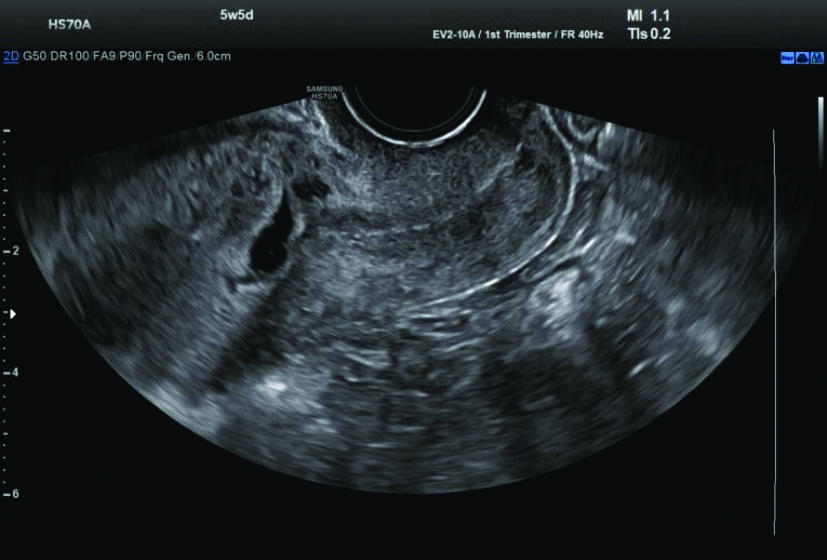

Ultrasound (USG) examination: The USG revealed a single gestational sac in the lower uterine segment at the region of the previous caesarean scar, extending into the anterior myometrial wall with surrounding increased vascularity and decidual reaction, suggestive of scar ectopic pregnancy. The foetal pole and yolk sac were not visualised. The mean gestational sac measured 9.9 mm, corresponding to 5.5 weeks [Table/Fig-4,5].

Ultrasound (USG) revealed a single gestational sac in the lower uterine segment.

Increased vascularity and decidual reaction on Ultrasound (USG).